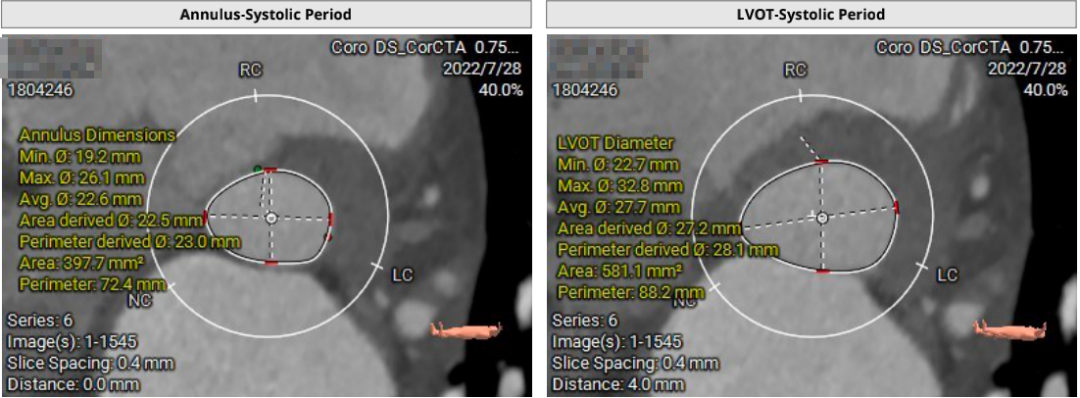

患者71岁女性,诊断为主动脉瓣重度狭窄合并心功能不全,瓣口面积仅0.5cm²,跨瓣压差超过50mmHg,且EF仅27%,心功能极差。术前CT检查瓣环周长72.2mm,LVOT呈喇叭型。CT检查同时发现患者入路血管狭窄,股动脉直径5.3cm,锁骨下和颈内动脉直径都小于5.0cm,对操作造成了一定困难。

结合充分的术前讨论,和策略制定。术中团队建立双侧股动脉入路,以右股为主,使用18F球囊预扩张时未出现腰征,微量反流,因此选择植入24F瓣膜。由于LVOT呈喇叭型,心夹角偏大,最初选择-1mm释放,在释放过程中稍有位移,最终固定在0位,瓣膜充分展开,形态和位置都很好,术后跨瓣压差7-8mmHg,无反流,手术顺利完成。

患者64岁男性,Type 0 型二叶瓣、横位心。主动脉瓣中度狭窄,重度反流,瓣环周长92.0mm,平均径29.0mm。LVOT周长98.7mm,升主扩张,窦部结构极限,锚定能力极限。入路两侧血管轻度迂曲,分叉高度可,两侧血管内径均>8mm。

首先,最重要的是观察瓣环结构,理论上如果瓣环周长超过85mm,尽量就不做;第二,看流出道情况,最好是直筒状的,瓣环和瓣下4mm的直径比值,理论上不能超过1:1.1,如果超过1.1以上就变成喇叭状,也不建议做;第三,避免存在升主动脉显著扩张,如果扩张明显,无法提供有效的锚定。总体来说,最主要的一定是瓣环直径,瓣叶有没有增厚,瓣叶有没有钙化,瓣环能否有效固定住植入的瓣膜。瓣环的固定和锚定条件,是反流患者能否进行TAVR的决定因素。